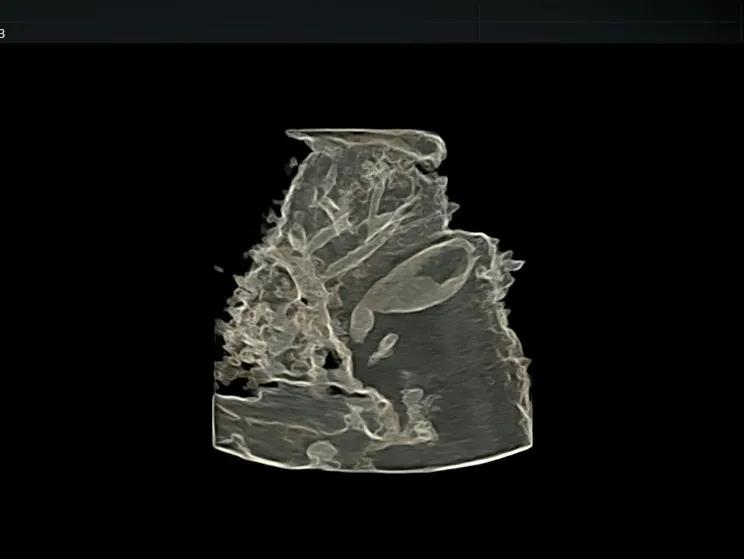

腹部容积成像

也就是4D超声波技术,是目前世界上最先进的彩色超声技术。四维成像技术(4D),能直观、立体显示人体器官的三维结构及动态、实时地观察立体结构,而以往的二维成像技术只能显示人体器官的某一切面。